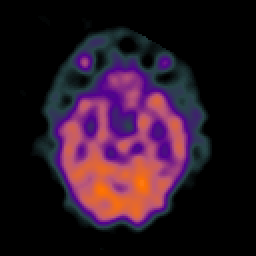

SPECT TC Study #5 -- Slice #21

[Home][Help][Clinical][Tour 1][Tour 2][Tour 3] Slice 21